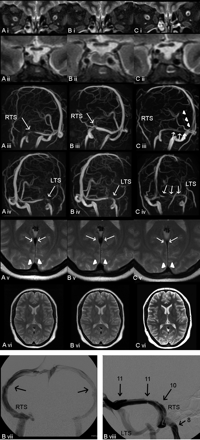

The 23-year-old woman (62 kg) presented with headache, diplopia, facial palsy, left auricular pain, and left-sided tinnitus. Clinical examination revealed bilateral papilledema, visual field reduction, and cranial nerve palsies of VI and VII. Findings of routine MR imaging were normal (Fig 1A). Lumbar CSF pressure was 41 cm H2O. Angiography depicted a stenotic left TS and aplasia of the right TS. No signs of acute sinus thrombosis were seen, and no fistula was found. Intravenous pressure-monitoring demonstrated elevated pressure in the superior sagittal sinus and a pressure gradient across the TS stenosis (Fig 1B), thus proving the hemodynamic significance of the stenosis. Stent angioplasty lead to reconstruction of the vessel lumen and normalization of intracranial venous pressure (Fig 1C, -D). Premedication with acetylsalicylic acid (2 × 100 mg), clopidogrel (1 × 75 mg), and intravenous heparin was given to prevent in-stent thrombosis.

Case 1: A and B, Axial T2-weighted turbo spin-echo (A) and venography (B) using a microcatheter in the torcular herophili inserted through the left TS (arrows, known aplasia of the right TS). The left TS in the lateral projection shows high-grade narrowing distal to a filling defect assumed to be an arachnoid granulation. C, Pressure monitoring at different locations (in centimeters H2O). D, Placement of a self-expanding nitinol stent (Absolute, Guidant, Indianapolis, Ind; 8 mm in diameter, 6-cm in length). Stenosis is abolished after stent placement. E, Poststent placement on routine cranial CT. F and G, On follow-up, contrast-enhanced CT (F) and proton-weighted MR imaging (G) in the same axial section position demonstrate a new stenosis in the medial aspect of the left transverse sinus (arrows) proximal to the stent. H and I, Venous phase of right internal carotid artery angiography in the lateral projection (H) and maximum intensity projection of MRV in the lateral projection (I) confirm the finding. Arrows indicate pre-stent stenosis. J, Following lumbar puncture, MRV shows significantly better flow signal intensity in the left transverse sinus proximal and within the stent (arrows) with albeit some signal-intensity reduction believed to be due to the stent material. K, Cranial CT after insertion of a ventriculoperitoneal shunt.

The patient reported significant improvement. However, headache and visual disturbances worsened 1 week later. Digital subtraction angiography, CT, and MR imaging showed a new stenosis of the TS just proximal to the stent (Fig 1F–I). Because no signs of acute thrombosis or any structure compressing the sinus such as hematoma were found, we believed that recurring elevation of CSF pressure led to restenosis. Color-coded transcranial duplex sonography confirmed this interpretation: An accelerated intrastenotic blood-flow velocity (150 cm/s) was found and could be reduced to almost normal levels (30 cm/s) by performing another lumbar puncture. In accordance with this finding, MR venography (MRV) depicted a marked reduction of the prestent stenosis after lumbar puncture (Fig 1J). MRV was performed in all our patients by using phase-contrast imaging on a 1.5T scanner (Achieva, Philips Medical Systems, Best, the Netherlands) with a uniform protocol (3D fast-field echo; TR/TE, 17/8; flip angle 10°; matrix, 256 × 256; S1, 1.6 mm; velocity encoding value/phase-contrast velocity, 15 cm/s), interpreting source images and maximum intensity projections.

Consequently, a ventriculoperitoneal shunt was inserted (Fig 1K), and the patient was discharged with only little residual head pain. Nine months later, she was free of pain and diplopia. Control MRV showed good venous drainage. Accordingly, blood velocity in the TS was normal as measured with transcranial color-coded duplex sonography (5–20 cm/s).

A 16-year-old girl (87 kg) with headache, diplopia, reduced visual acuity, and hyposmia had papilledema and elevated lumbar CFS pressure (50 cm H2O). Bilateral TS stenoses were suspected on MRV (Fig 2A). Treatment with acetazolamide (2 × 250 mg) was unsuccessful in reducing her symptoms. MRV following lumbar puncture showed some improvement of the blood-flow signal intensity in the lateral TS (Fig 2B). Again, after a second lumbar puncture with hardly any increased pressure left, the stenoses almost completely resolved on MRV (Fig 1C) and vision improved.

Case 2: MIP of MRV in oblique anteroposterior left and right views obtained at a lumbar CSF pressures of 50 cm H2O (A), after lumbar puncture (B), after a 2nd lumbar puncture with no residual pressure being monitored (C), and after placement of a ventriculoperitoneal shunt (D). Stenoses in both the left and right transverse sinuses (LTS, RTS), as marked with arrows, are reduced in accordance with a lowered CSF pressure, with complete resolution in C. Probably as a result of a relatively high opening pressure of the valve of the ventriculoperitoneal shunt, transverse sinuses show some residual narrowing (D). T2-weighted axial images before (E) and after (F) insertion of a ventriculoperitoneal shunt into the right ventricle show no difference in ventricle size.

The effect of lumbar puncture vanished 3 days later when the patient again had visual disturbances, and Doppler sonography showed elevated blood-flow velocities in the TS (40 cm/s). After ventriculoperitoneal shunt surgery, headache and papilledema did not reoccur (8-month follow-up) and MRV showed continuous blood-flow signal intensity with some residual stenosis in the right TS (Fig 2D).